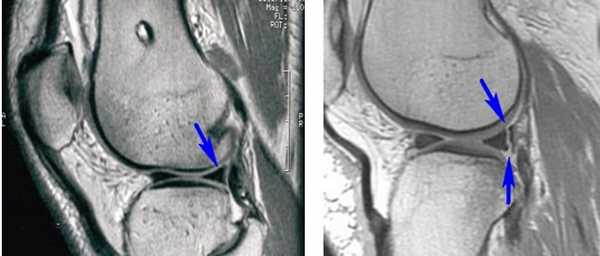

• Разрыв типа «ручки лейки» с дислокацией:

- На МР-томограммах при разрыве мениска типа «ручки лейки» в сагиттальной проекции отмечается дефицит заднего рога мениска (рис. 5, А) и симптом «удвоения задней крестообразной связки» за счет смещения поврежденной части мениска в межмыщелковую вырезку (рис. 5, Б). На другом сагиттальном срезе также виден смещенный в межмыщелковую вырезку фрагмент мениска (рис. 5, В)